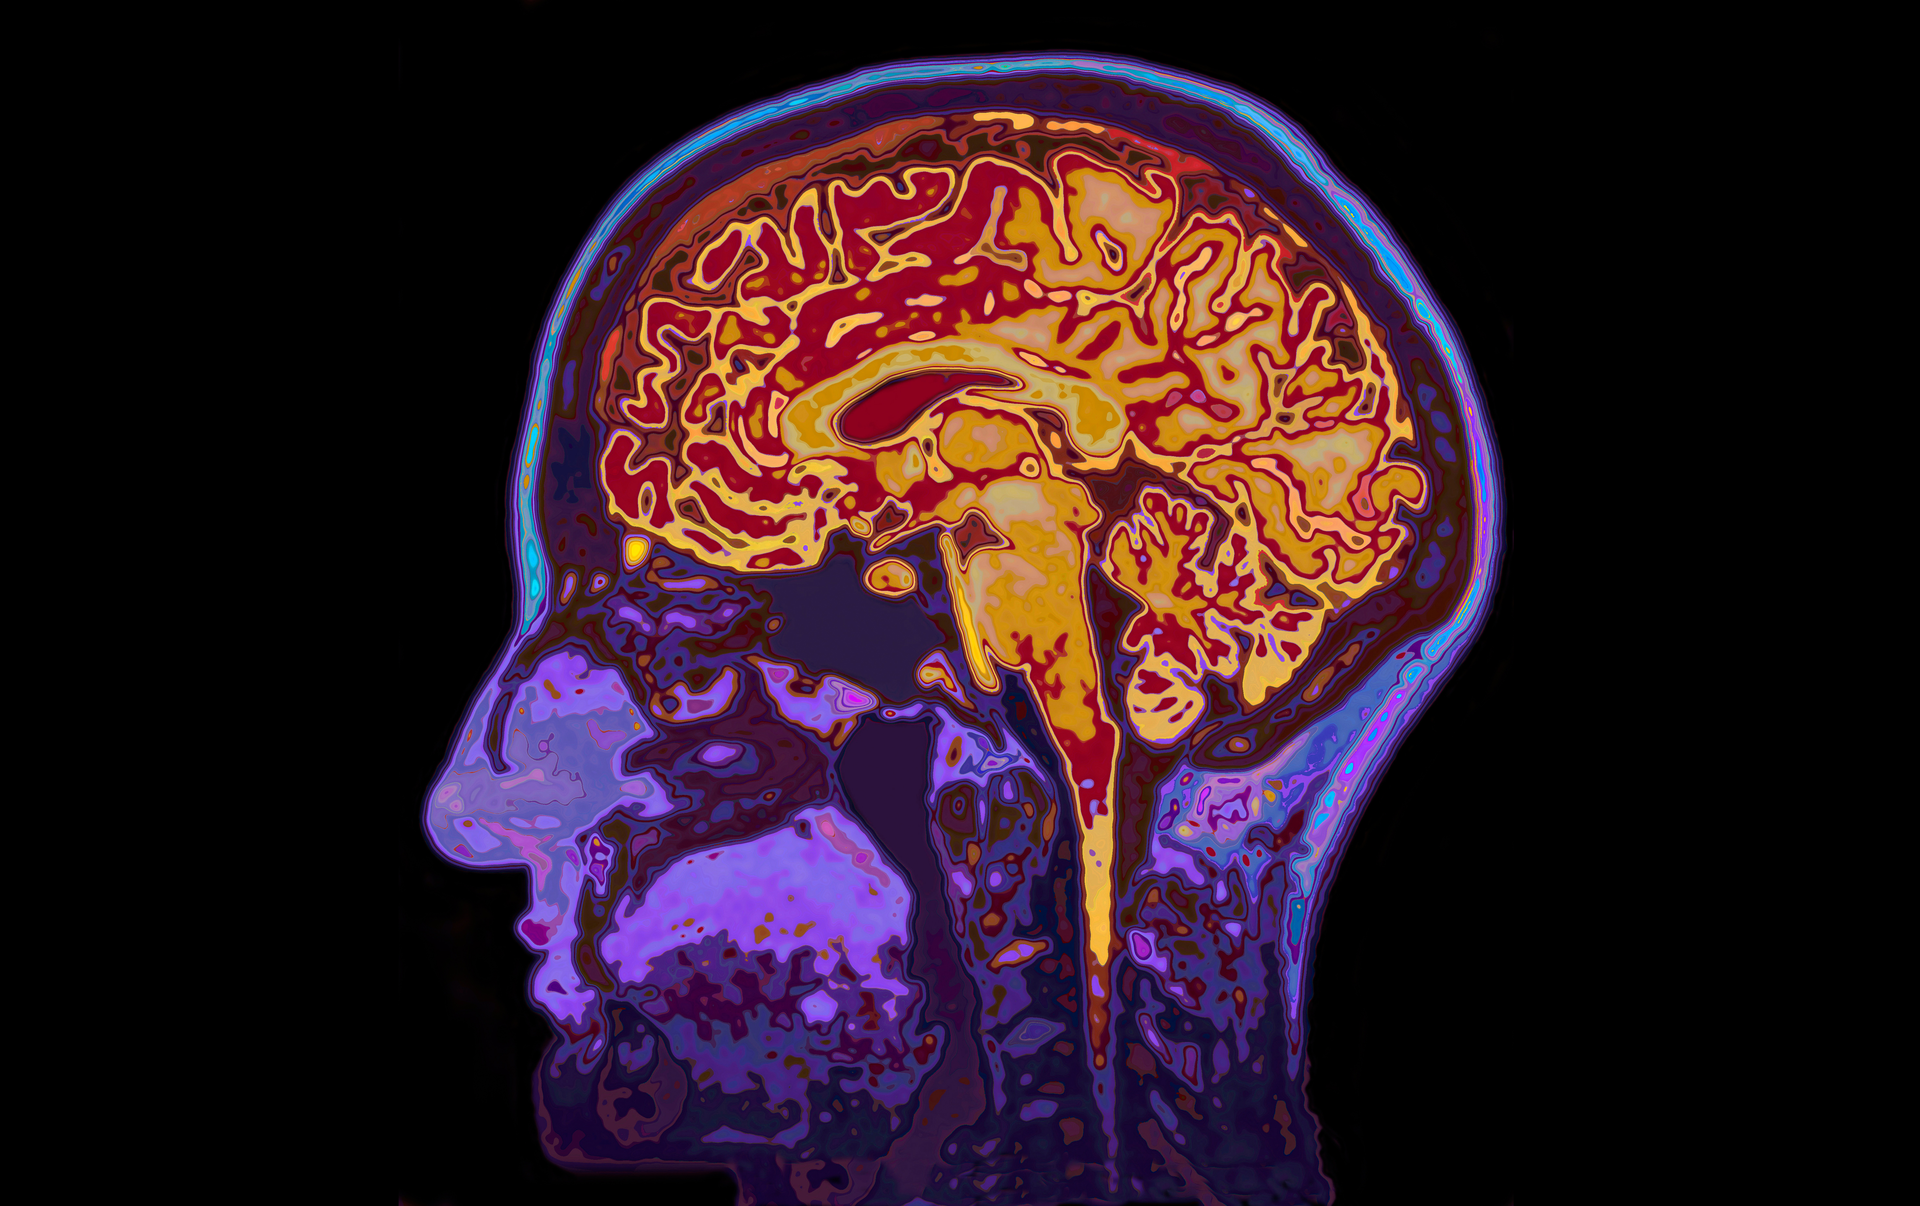

When cancer spreads to the brain, treatment options fall off. Most of the drugs designed to target metastases do not cross the blood-brain barrier or are ineffective at treating brain metastases.

To understand the molecular processes that influence how cancer cells pass through the blood-brain barrier, researchers used two microfluidic chips that mapped cancer cell migration to the brain and looked at what was happening in the blood-brain niche. Results are published in the journal Advanced NanoBiomed Research.

Using breast cancer cell lines, they found that Dkk-1, a cytokine released by the astrocytes, triggers the cancer cells to migrate. Dkk-1 is known to play a role in in Wnt signaling, a key signaling pathway linked to cancer progression.